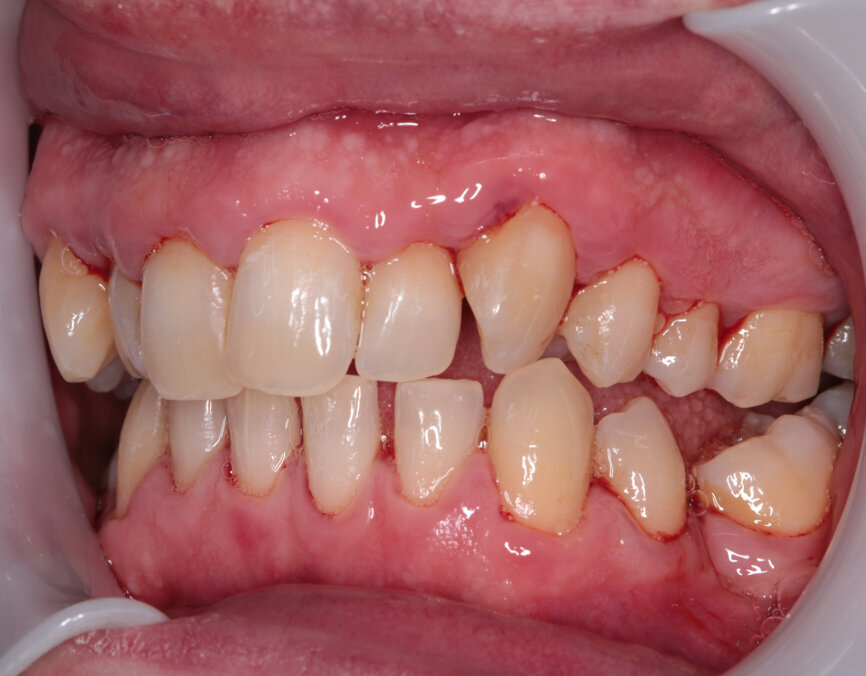

Fig. 7: Post-scaling anterior view

I explained that the maxillary teeth could and should be aligned, as this would likely result in easier cleaning of the teeth, plus it would improve the appearance. The patient and I agreed that the mandibular teeth could remain untouched, as this would keep the cost down, but mainly because they did not bother him. The priority was to stabilise his periodontal condition. A basic periodontal examination Code 3 and heavy bleeding were recorded in each sextant. At that visit, I performed a gross scaling using the ultrasonic scaler and used a model to demonstrate both the use of flossettes and an oscillating toothbrush.

Twenty days later, tooth #48 was restored and I was pleased to find the patient’s cleaning had clearly been consistent and diligent. The improvement was extremely impressive and exceeded my expectations. A fine scaling was carried out with further encouragement to maintain this level of home care.

Two weeks later, the colour and contour of the patient’s gingival margins were as healthy as could be considering the crowding of the teeth. We discussed what treatment with ClearSmile Aligners would involve, such as interproximal reduction (IPR), compliance and risks, and a referral for specialist orthodontics was offered. Preferring to proceed with clear aligners, the patient signed off his full consent, and a two-stage putty impression was taken using a separation wafer. The Archwize digital planning software was used to predict tooth movement and necessary IPR throughout treatment. It suggested that 18 maxillary aligners would be needed.